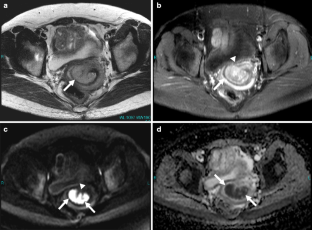

Fig. 4a–d